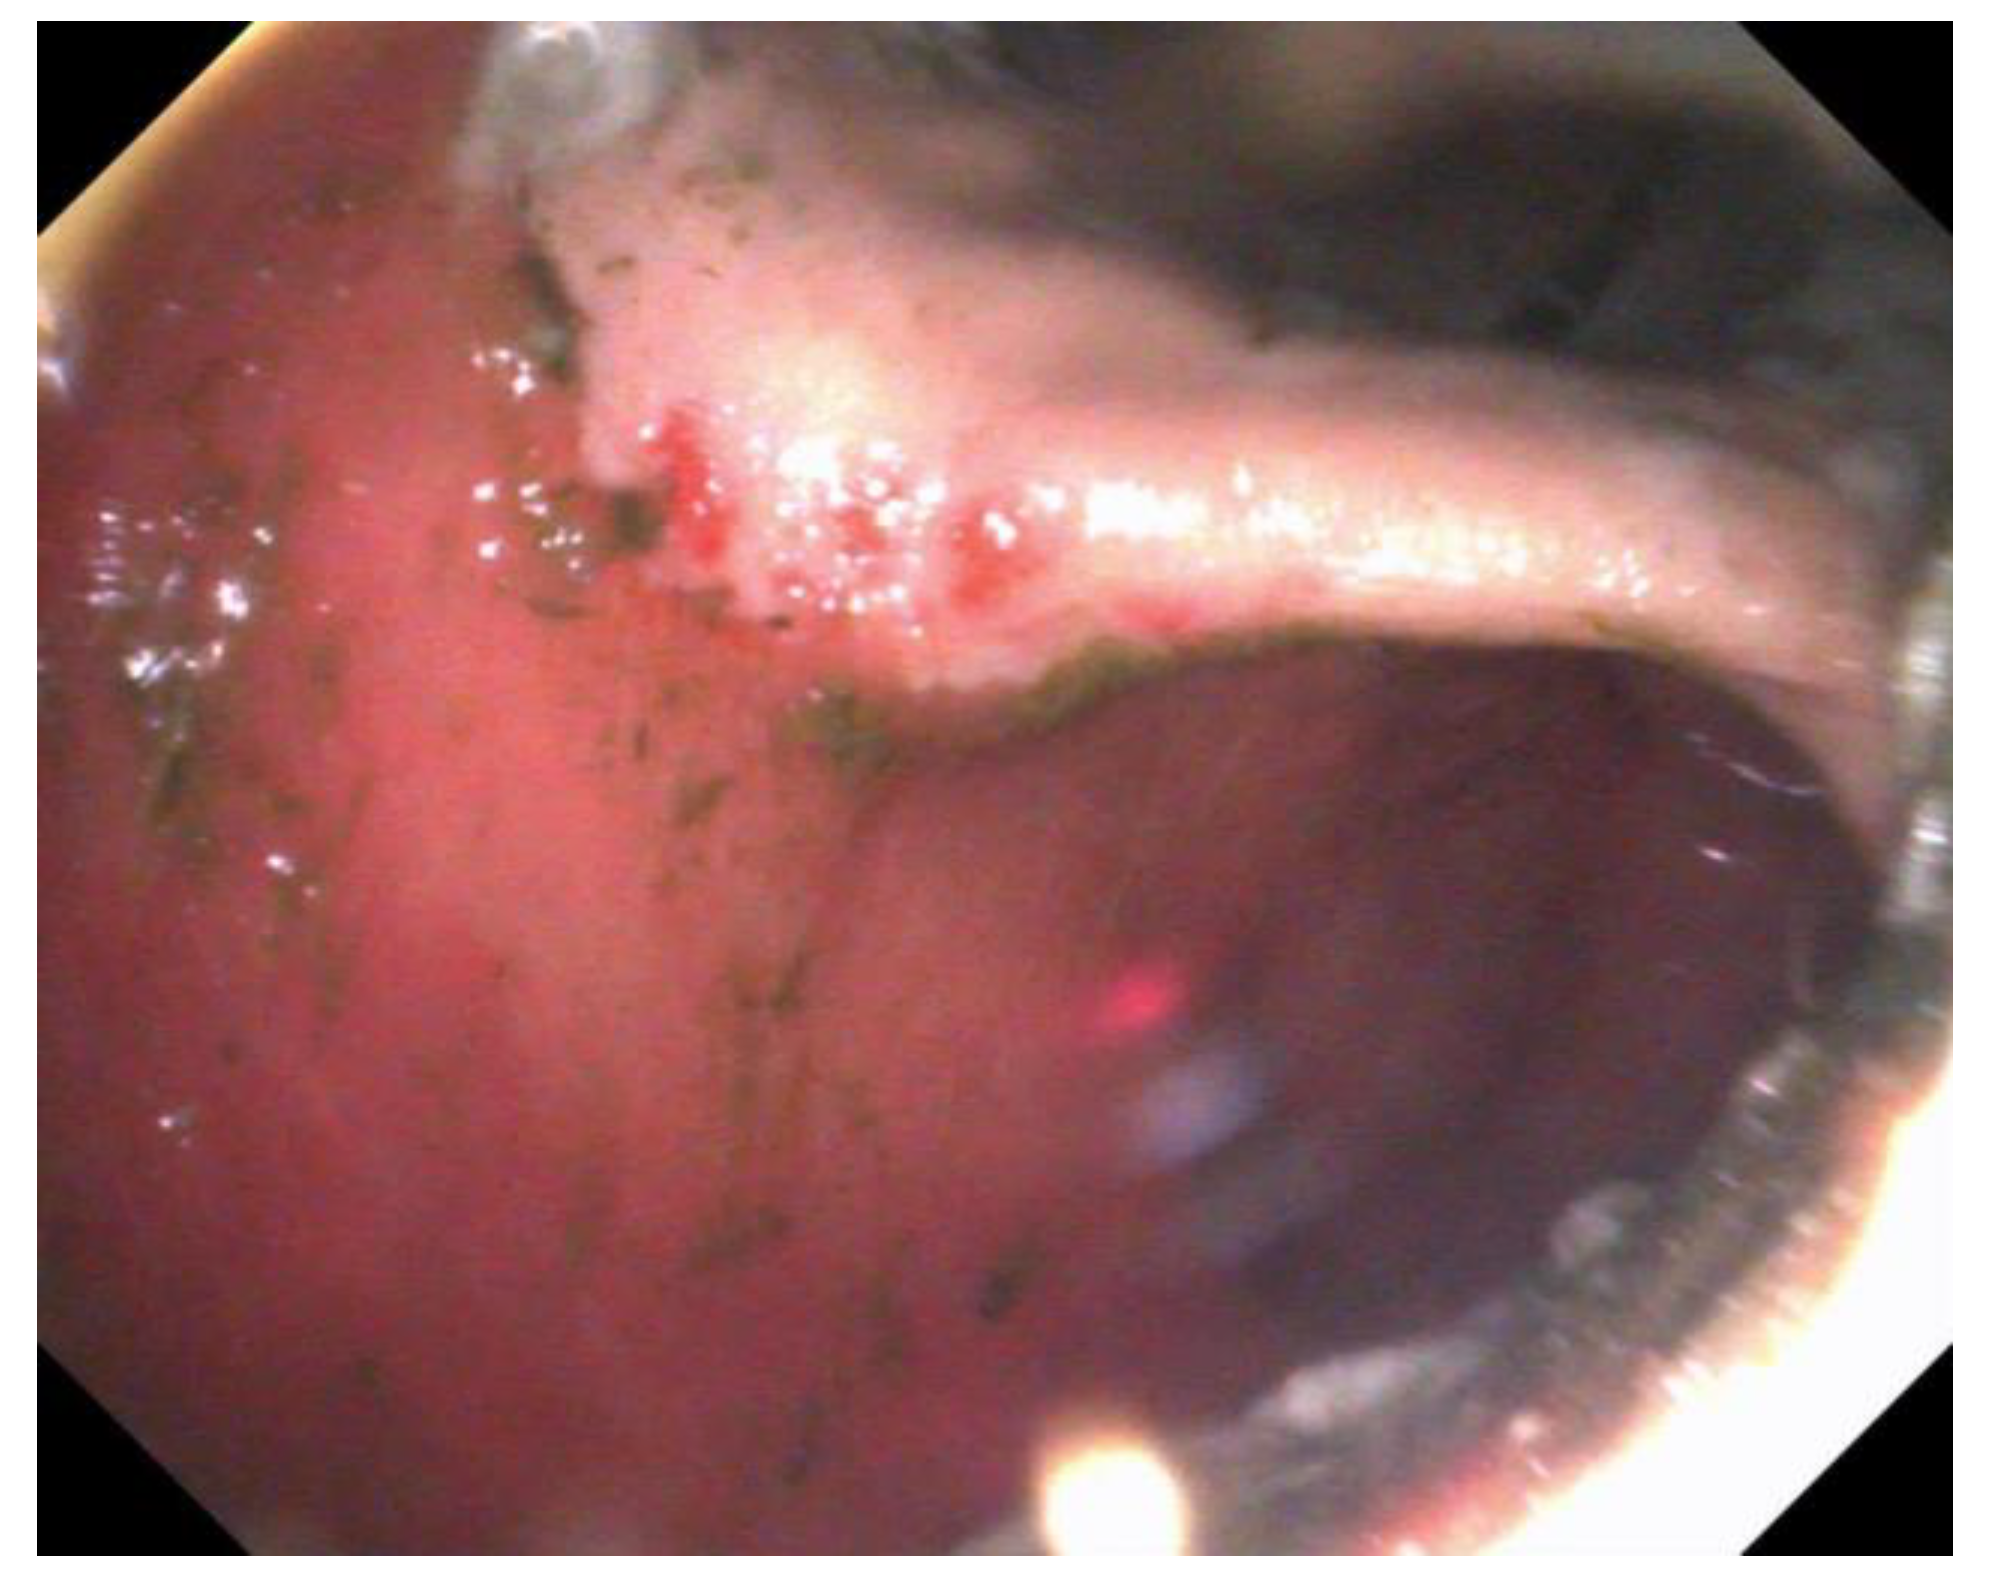

For EGGD, the recommendation at this time remains not to assign a grade to these lesions, but instead, that lesions be described by anatomical location, distribution, severity and appearance [1]. Appearance is described as hyperemic/hemorrhagic (Figure 2 and Figure 3), erosive/ulcerated or fibrinosuppurative, and by contour; depressed, flat or raised [1]. The existence of glandular gastric polyps is also considered as a form of EGGD [120,121].

Figure 3.

Multiple, linear, flat, hemorrhagic lesions of the pyloric mucosa.